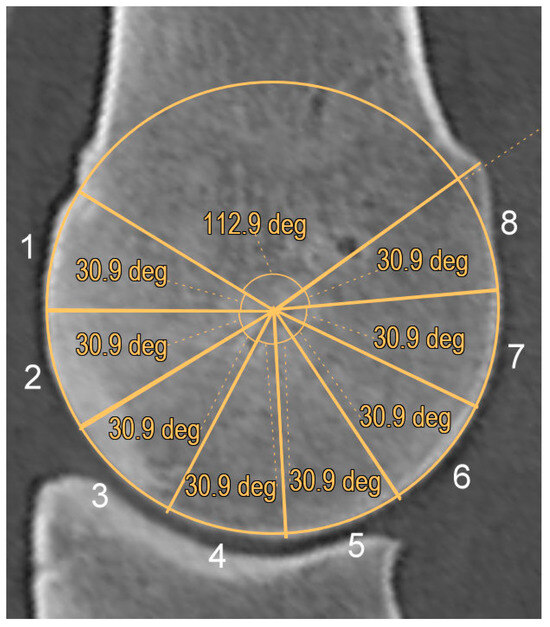

3.2. Hounsfield Unit Measurements

3.3. Hypoattenuating Lesions

3.4. Subchondral Bone Thickening, Trabecular Bone Hyperattenuation